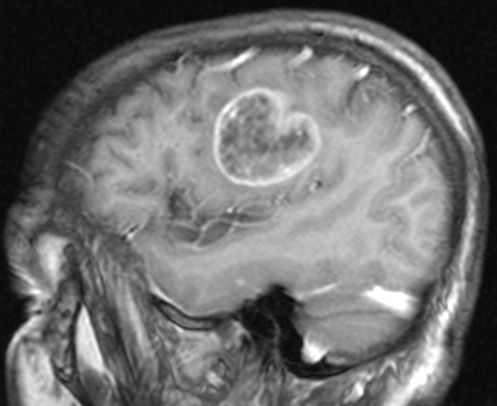

| 10 Jahre Intervall | 76-jähriger Mann, der vor 10 Jahren ein

Adenokarzinom des re Lungenunterlappens hatte, welches kurativ operiert

wurde. Jetzt singuläre Hirnmetastase mit Kontakt zum Seitenventrikel.

Primärtumor und Metastase Adenokarzinom TTF1 negativ.![]() | |||